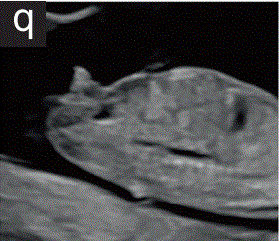

7.1.3  到妊娠12周时,胎儿膀胱在下腹部正中可见低回声圆形结构,纵向直径<为7mm(图2p和2q)。

胎儿mt是什么检查什么疼吗【文献学习/规范指南】ISUOG实践指南(2023更新): 11-14周胎儿超声检查(全文)_https://www.jmylbn.com_新闻资讯_第22张

胎儿mt是什么检查什么疼吗【文献学习/规范指南】ISUOG实践指南(2023更新): 11-14周胎儿超声检查(全文)_https://www.jmylbn.com_新闻资讯_第23张

图2 11+0至14+0周时,可作为详细胎儿超声检查的一部分获得的解剖图。

(p)胎儿骨盆的横断切面,显示存在胎儿膀胱。

(q)胎儿腹部矢状面图,显示胎儿膀胱、生殖器结节、膈肌和脊柱。在该胎龄时,对胎儿膀胱的任何测量都应在纵向和矢状面上进行。

10.生殖器

10.1 对外生殖器和胎儿性别的评估是基于在矢状面的方向的生殖器结节(图2q)。

胎儿mt是什么检查什么疼吗【文献学习/规范指南】ISUOG实践指南(2023更新): 11-14周胎儿超声检查(全文)_https://www.jmylbn.com_新闻资讯_第29张